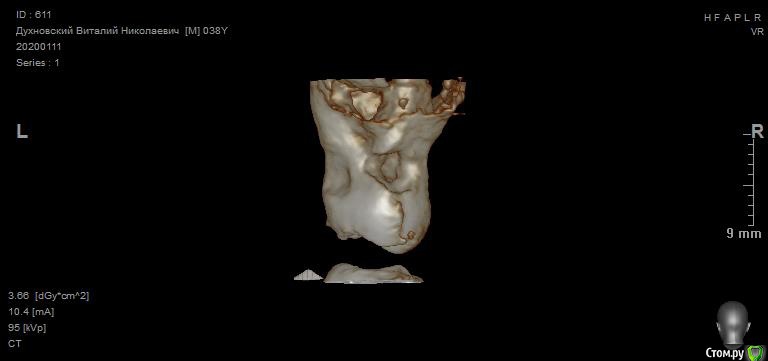

Просьба ко всем не равнодушным! Глянуть КТ верхней челюсти, 27 зуб  и место где удалили 16, может ещё где-то могут быть проблемы.  На фото видно где покраснение на дёснах, в этих местах возникают боли при движении головой. Бывает боль слева если засыпаю на левой стороне. Набуханий или флюсов нигде не видно.Прошу делиться мнениями, для меня это очень - очень важно. Стоматолог визуальных проблем на месте удалённого зуба не видит, всё зажило.

Зуб 27 требует внимания, необходим очный осмотр.